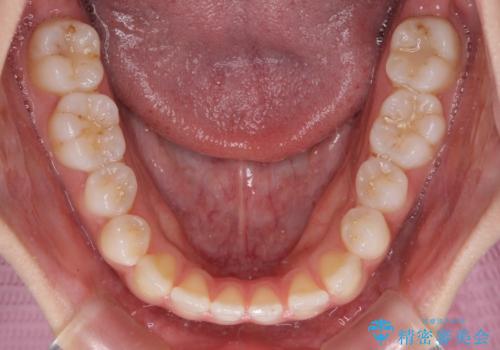

- 前歯の上下スペースと前歯の隙間を気にして来院された患者様です。

インビザラインにより上下の前歯の隙間を閉じていくこととしました。

上下の隙間に舌が入り込むことが、すきっ歯やオープンバイトの原因であったため、舌の筋肉のトレーニングも並行して行い、後戻りの抑制を図りました。